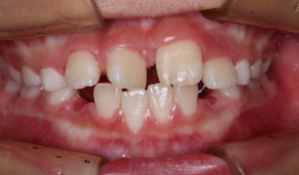

マウスピース型矯正装置(インビザライン)の症例

マウスピース型矯正装置(インビザライン)を使用した歯列矯正

ガタガタ(叢生)